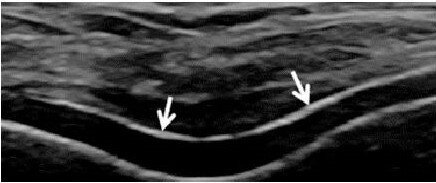

УЗИ - отличный метод для безопасной диагностики, признаком подагры является “двойной контур” - отложение кристаллов мочевой кислоты на суставном хряще, “снежная буря” - скопление кристаллов в суставной полости. Если это видно при исследовании, диагноз почти "в кармане", но, к сожалению, такая картина визуализируется не всегда.

При пирофосфатной артропатии - кристаллы, как правило, внутри хряща.

При гидроксиаппатитной артропатии - внутри мягких тканей вокруг сустава, как правило, сухожилия.